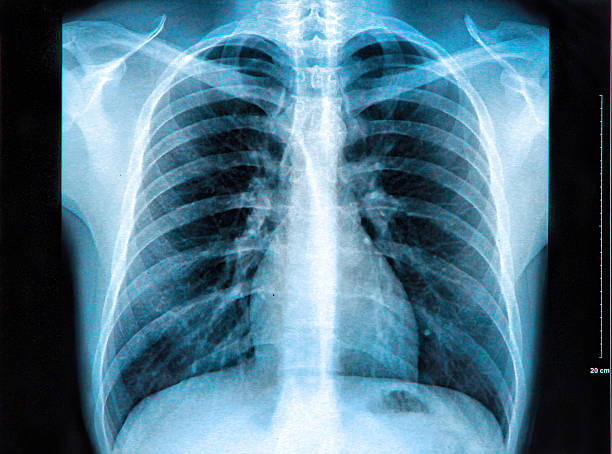

Una radiografía es una prueba que toma imágenes de las estructuras internas del cuerpo. Para poder obtenerlas utilizamos rayos X que pasan a través del cuerpo y crean imágenes de los huesos y sus órganos con fines de diagnóstico. Es una prueba indolora y rápida.

Tipos de RADIOGRAFÍAS:

• Tórax